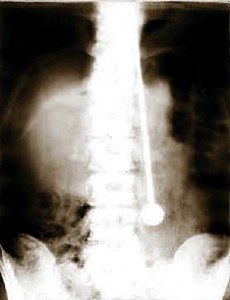

Рентгеновский снимок, подтверждающий уникальные свойства организма Неуязвимого

Конечно, Дажо проверяли врачи, причем не раз. В конце мая 1947 года он продемонстрировал свои таланты в Цюрихском кантональном госпитале. Как обычно, Ми-рин разделся до талии. Когда ассистент пронзил рапирой сердце, легкие и почки, он, как обычно, не почувствовал боли и не проронил ни капли крови. Чтобы исключить возможность гипноза, было решено сделать рентген, но медики не знали, как доставить его до рентгеновского кабинета — ведь носилки не приспособлены к транспортировке людей, пронзенных рапирами. Дажо успокоил их, сказав, что сам дойдет куда нужно — с рапирой естественно. Снимки исключили всякие сомнения: клинок прошел через несколько жизненно важных органов, но не причинил никаких повреждений.